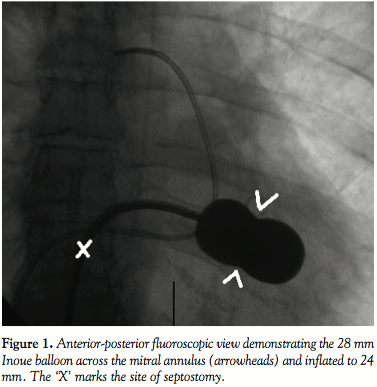

The patient underwent transthoracic echocardiographic and fluoroscopic-guided balloon valvuloplasty (Figure 1) using a standard transseptal technique and a 28 mm Inoue Balloon (Toray Industries). After valvuloplasty, the mean mitral gradient measured by simultaneous sampling in the left atrium and left ventricle was reduced from 9 mm Hg to 4 mm Hg, and the calculated valve area increased from 1.2 cm2 to 1.9 cm2. The mitral regurgitation by ventriculography remained unchanged (1+ before and after valvuloplasty). A shunt run at the end of the procedure showed a Qp/Qs of 1.2:1 (no shunt was present at the beginning of the procedure). The patient did well overnight following the procedure, and an echocardiogram the following morning showed a mean mitral valve gradient of 5 with a peak gradient of 9 and mild mitral regurgitation. Note was made at that time of “a small atrial septal defect” on both the apical 4-chamber and subcostal views with evidence of left-to-right shunting by color Doppler (Figure 2). The patient was subsequently discharged home. During routine clinical follow-up 1 month later, a review of systems revealed the patient was now experiencing migraine headaches that began a few days after her discharge. She had been seen by a neurologist, who prescribed abortive therapy to use as needed. She reported having 3-4 headaches a week that generally began with an aura of flashing lights and odd scents, followed by unilateral eye and left temporal throbbing. Brain magnetic resonance imaging scan and magnetic resonance angiogram were obtained and showed no stroke or vascular abnormalities. On further questioning, the patient revealed she had migraines as a child that caused her to frequently miss school, but had eventually grown out of them. A repeat echocardiogram was performed during her visit and showed a persistence of atrial level shunting. Color Doppler this time suggested bidirectional shunting and a bubble study confirmed right-to-left shunting.